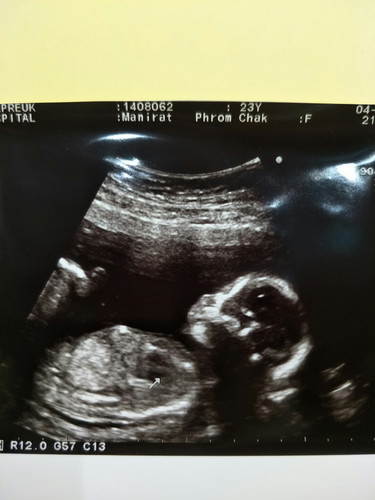

ซาวน์ครั้งแรก 18วีค ค่า?

วันนี้หมอนัดซาวน์ครั้งแรกตื่นเต้นมากกกๆ ดิ้นโชว์เก่ง ทำปากมุบมิบๆน่าตีมากๆ ขอพื้นที่เห่อลูกหน่อยนะค้าาาแม่ๆ ?☺☺?

ตอนเห็นครั้งเเรกน้ำตาไหลเลยค่ะ มีความรู้สึกแบบบอกไม่ถูกเลย